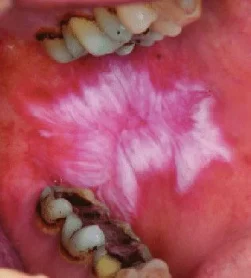

مقدمه لیکن پلان دهانی یک بیماری التهابی مزمن است که میتواند روی بافتهای نرم دهان تأثیر بگذارد؛ این بیماری میتواند باعث بروز زخمها، درد و ناراحتی در دهان شود و در برخی موارد، به مشکلات جدیتری منجر گردد. با توجه